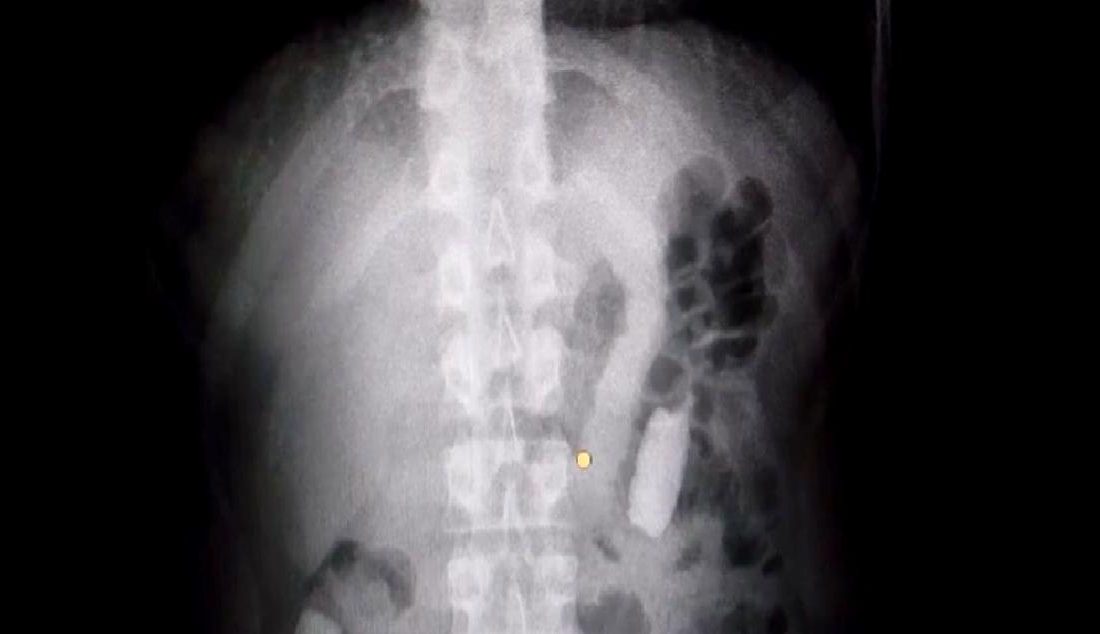

Yapılan operasyonda, M.R.B. yakalanarak gözaltına alındı. Şüphelinin hastanede yapılan muayenesinde, midesinden 77 adet kapsül şeklinde toplam 1 kilo 134 gram afyon sakızı çıkarıldı. Bu durum, uyuşturucu madde ticaretiyle mücadelede önemli bir başarı olarak değerlendirildi.